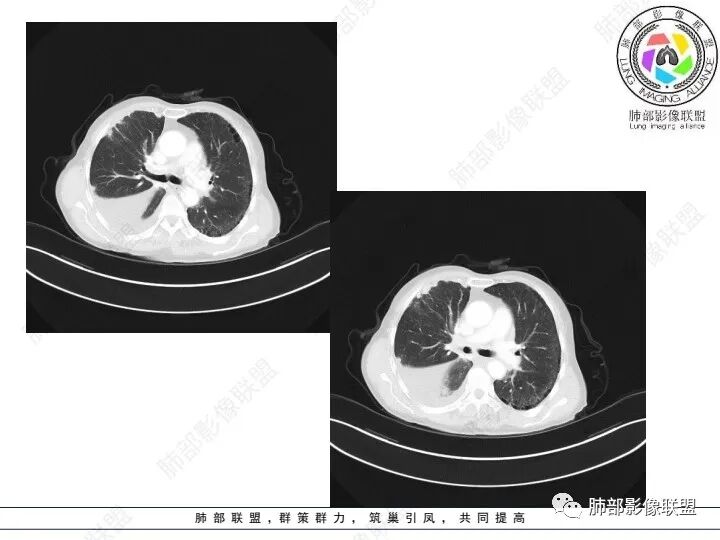

精彩讨论

右肺下叶胸膜下不规则肿块,与肺门相连,不均匀强化,胸壁受侵,右肺内多发小结节,下叶血管束增粗,小叶间隔增厚,右肺门及纵膈多发淋肿大淋巴结,融合,右侧胸水,考虑腺癌转移

患者老年女性,腹痛、黑便4小时。查肿瘤结果CA125明显升高,余正常。胸部CT:双肺胸膜下间质性改变,右肺胸膜下多发结节灶,以右肺下叶为大,增强渐进性强化,内低密度灶。右肺门淋巴结肿大伴钙化,右中间支气管狭窄,右侧包裹性胸腔积液。综合考虑恶性,腺癌可能大。鉴别转移。

肺门肿块环形包绕气管,右肺下叶可见一环状强化肿块,右侧胸膜多发强化结节,首先考虑结核并结核性胸膜炎

3、胸部增强CT示右肺下叶脊柱旁不规则软组织肿块,侵及壁层胸膜外,密度不均匀,不均匀强化,中心低密区可疑坏死,右侧胸腔积液、胸膜结节影或结节样增厚,增强扫描可见强化,右侧肺门及纵隔内可见淋巴结肿大、融合,右侧中尖段支气管及右肺下叶支气管受侵,管腔狭窄。

4、综上,老年男性,CA125升高,右肺下叶肿块侵犯胸壁,伴纵隔、右肺门及纵隔淋巴结肿大,右侧胸腔积液、胸膜增厚伴结节影,强化明显,应该为一较典型的肺癌伴肺胸膜腔及肺门纵隔淋巴结转移,尤其是肺腺癌。